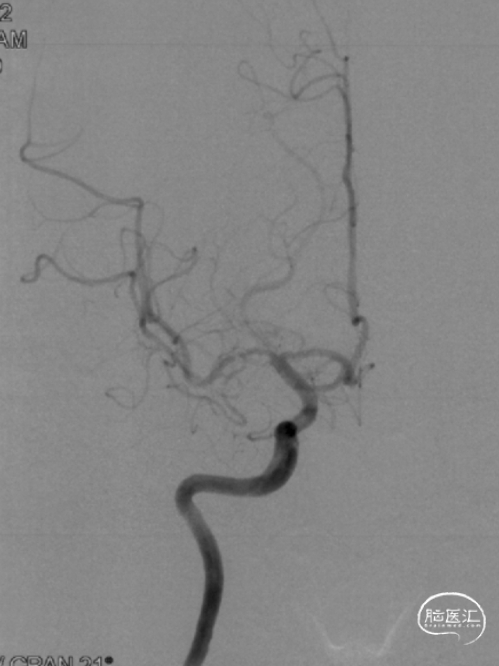

➤术前DSA检查

右侧大脑中动脉重度狭窄,左侧前循环未见明显异常。

病变部位: 右侧大脑中动脉M1段重度狭窄;狭窄率: 75.6%;狭窄长度: 6.10mm;参考远端血管直径: 1.27mm。

2022-07-27 术前正位

2022-07-27 术前侧位